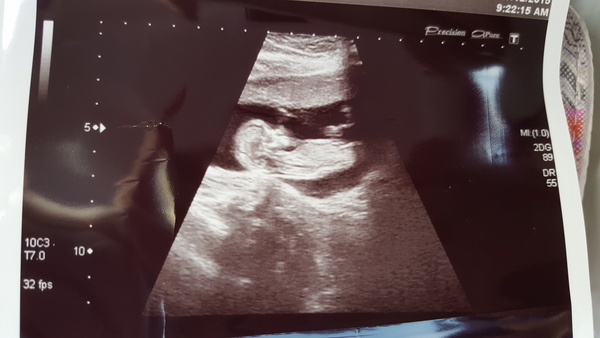

Hi everyone. All good news from my scan today. Showed a wriggly, healthy baby with all limbs intact! EDD is bang on for 16th June.

I have a little wriggler who didn't want measured today Grin all well, moved forward 3 dates so new EDD of 19/06/2016